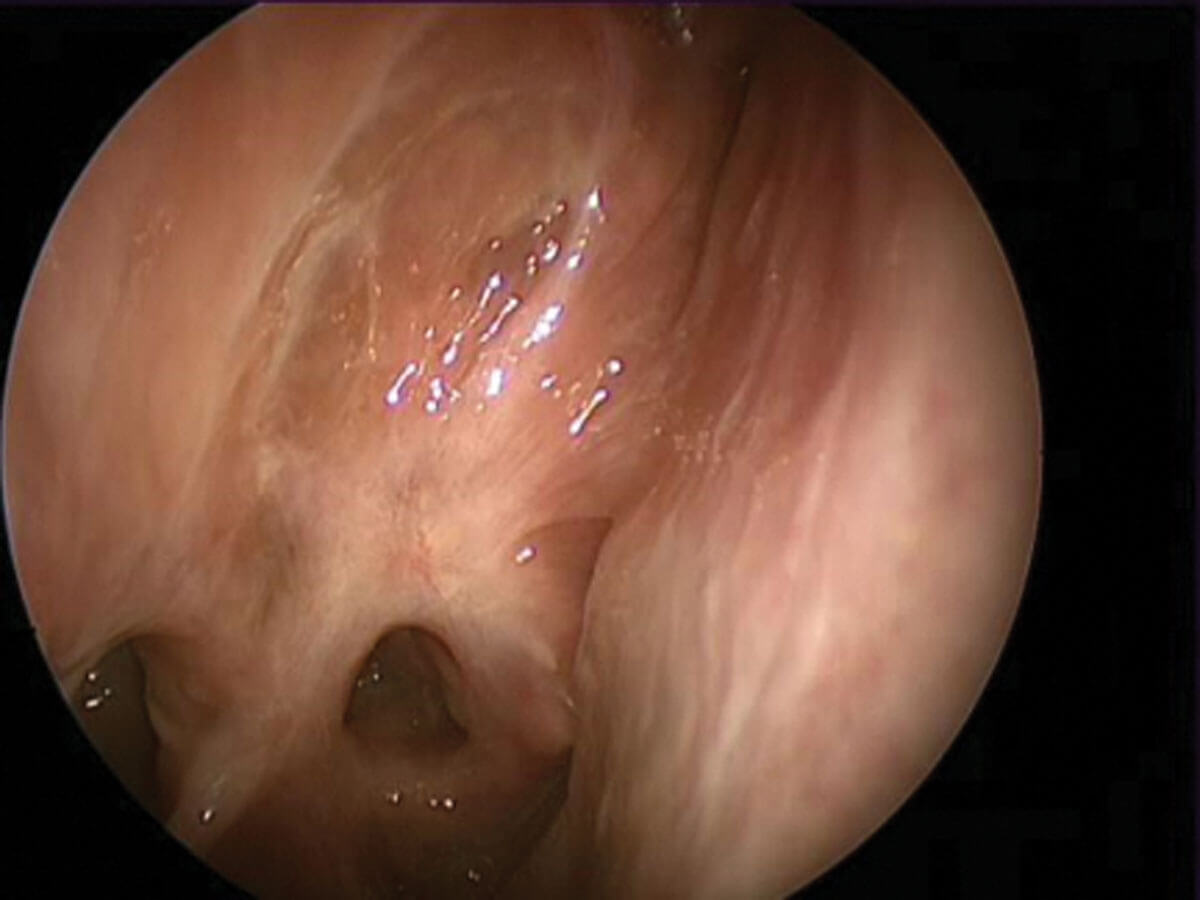

Scarred olfactory cleft following middle turbinate section.

Iatrogenic injuryIf

endoscopic sinus surgery is undertaken, it is essential that due care is taken with areas of the nasal cavity bearing olfactory epithelium, including the middle and superior turbinates and the upper nasal septum. More radical techniques that remove such areas not only have the potential to remove the cumulative olfactory neuroepithelial surface area but, in case of NERD and AFRS, it is not uncommon to see neo-turbinate formation from crops of nasal polyps that occlude the olfactory cleft. It is likely that more aggressive surgery goes hand in hand with more aggressive endotypes of CRS and that iatrogenic and neuroepithelial insults occur in tandem.

Radiological evidence of partial sinus surgery and middle turbinate removal.